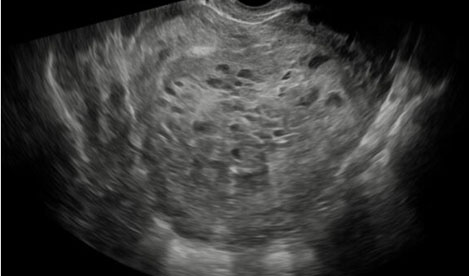

The patient’s serum quantitative bHCG is 59,401 with blood type O+. The remaining laboratory studies were unremarkable. Transvaginal ultrasound showed no evidence of intrauterine gestation with complex heterogenous material within the uterus measuring 8.8×4.9×6.8 cm (Figure 1 and Figure 2). The patient was counseled appropriately about suction dilatation and curettage in the context of suspected complete molar pregnancy, given the absence of a fetus on transvaginal sonogram, elevated serum bHCG level, vaginal spotting, and new onset hypertension. The patient underwent an uncomplicated suction dilatation and curettage. Intra-operatively, tan-colored grape-like vesicles measuring between 1 and 2 cm were noted in the suction tubing (Figure 3). Post-procedure bedside sonogram was performed and revealed a thin endometrial stripe. The patient tolerated the surgery well and was discharged in good health after appropriate clearance from postoperative anesthesia care unit. Post-operatively, appropriate pre-eclampsia laboratory tests were conducted due to the patient’s elevated blood pressure, revealing a urine protein-creatinine ratio of 0.245 and normal serum laboratory results. Given persistently elevated blood pressures post-procedure, the patient was started on Labetalol 200 mg twice daily upon discharge. Pathology assessment of the resected surgical specimen confirmed complete molar pregnancy. The patient’s blood pressures normalized one-month post-procedure and she is no longer taking the prescribed anti-hypertensive. Her post-operative bHCG was closely followed weekly over the course of eight weeks until the value was less than 1.0.

Figure 1: Sagittal view of the uterus demonstrating “snow-storm like” appearance of a complete molar pregnancy via transvaginal ultrasound.

Imaging through transvaginal ultrasound often can diagnose molar pregnancy before 12 weeks. Ultrasound can show either a honeycomb or a fine vascular appearance [7]. Ultrasound confirmation of a complete molar pregnancy after 12 weeks of gestation is characterized by a lack of fetal parts and scant embryonal development with a classic “snowstorm-like” appearance within the uterus. Specifically, the “snowstorm-like” appearance is indicative of hydropic villi and intrauterine hemorrhage. The ovaries can often contain multiple large theca-lutein cysts secondary to ovarian hyperstimulation from elevated bHCG levels [8]. Meanwhile, ultrasound confirmation of a partial mole can be slightly more difficult as there is usually the presence of a fetus and/or a large placenta [8].